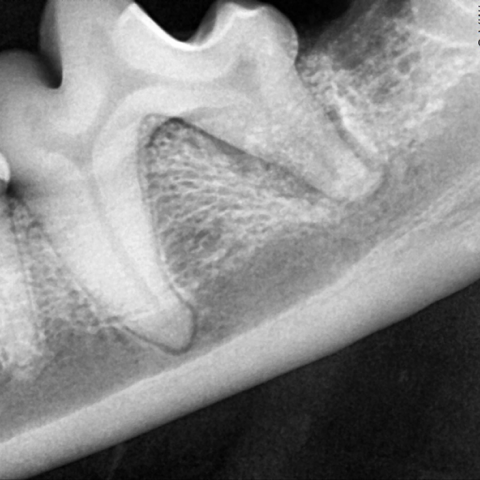

수술 전

수술 후

고해상도의 치아 전용 방사선 장비로 치아와 주변 구조의 손상을 정확하게 파악할 수 있어요. 이를 바탕으로 손상된 부위를 다시 재생시킬 수 있죠.

치료 전

GBR 치료 후